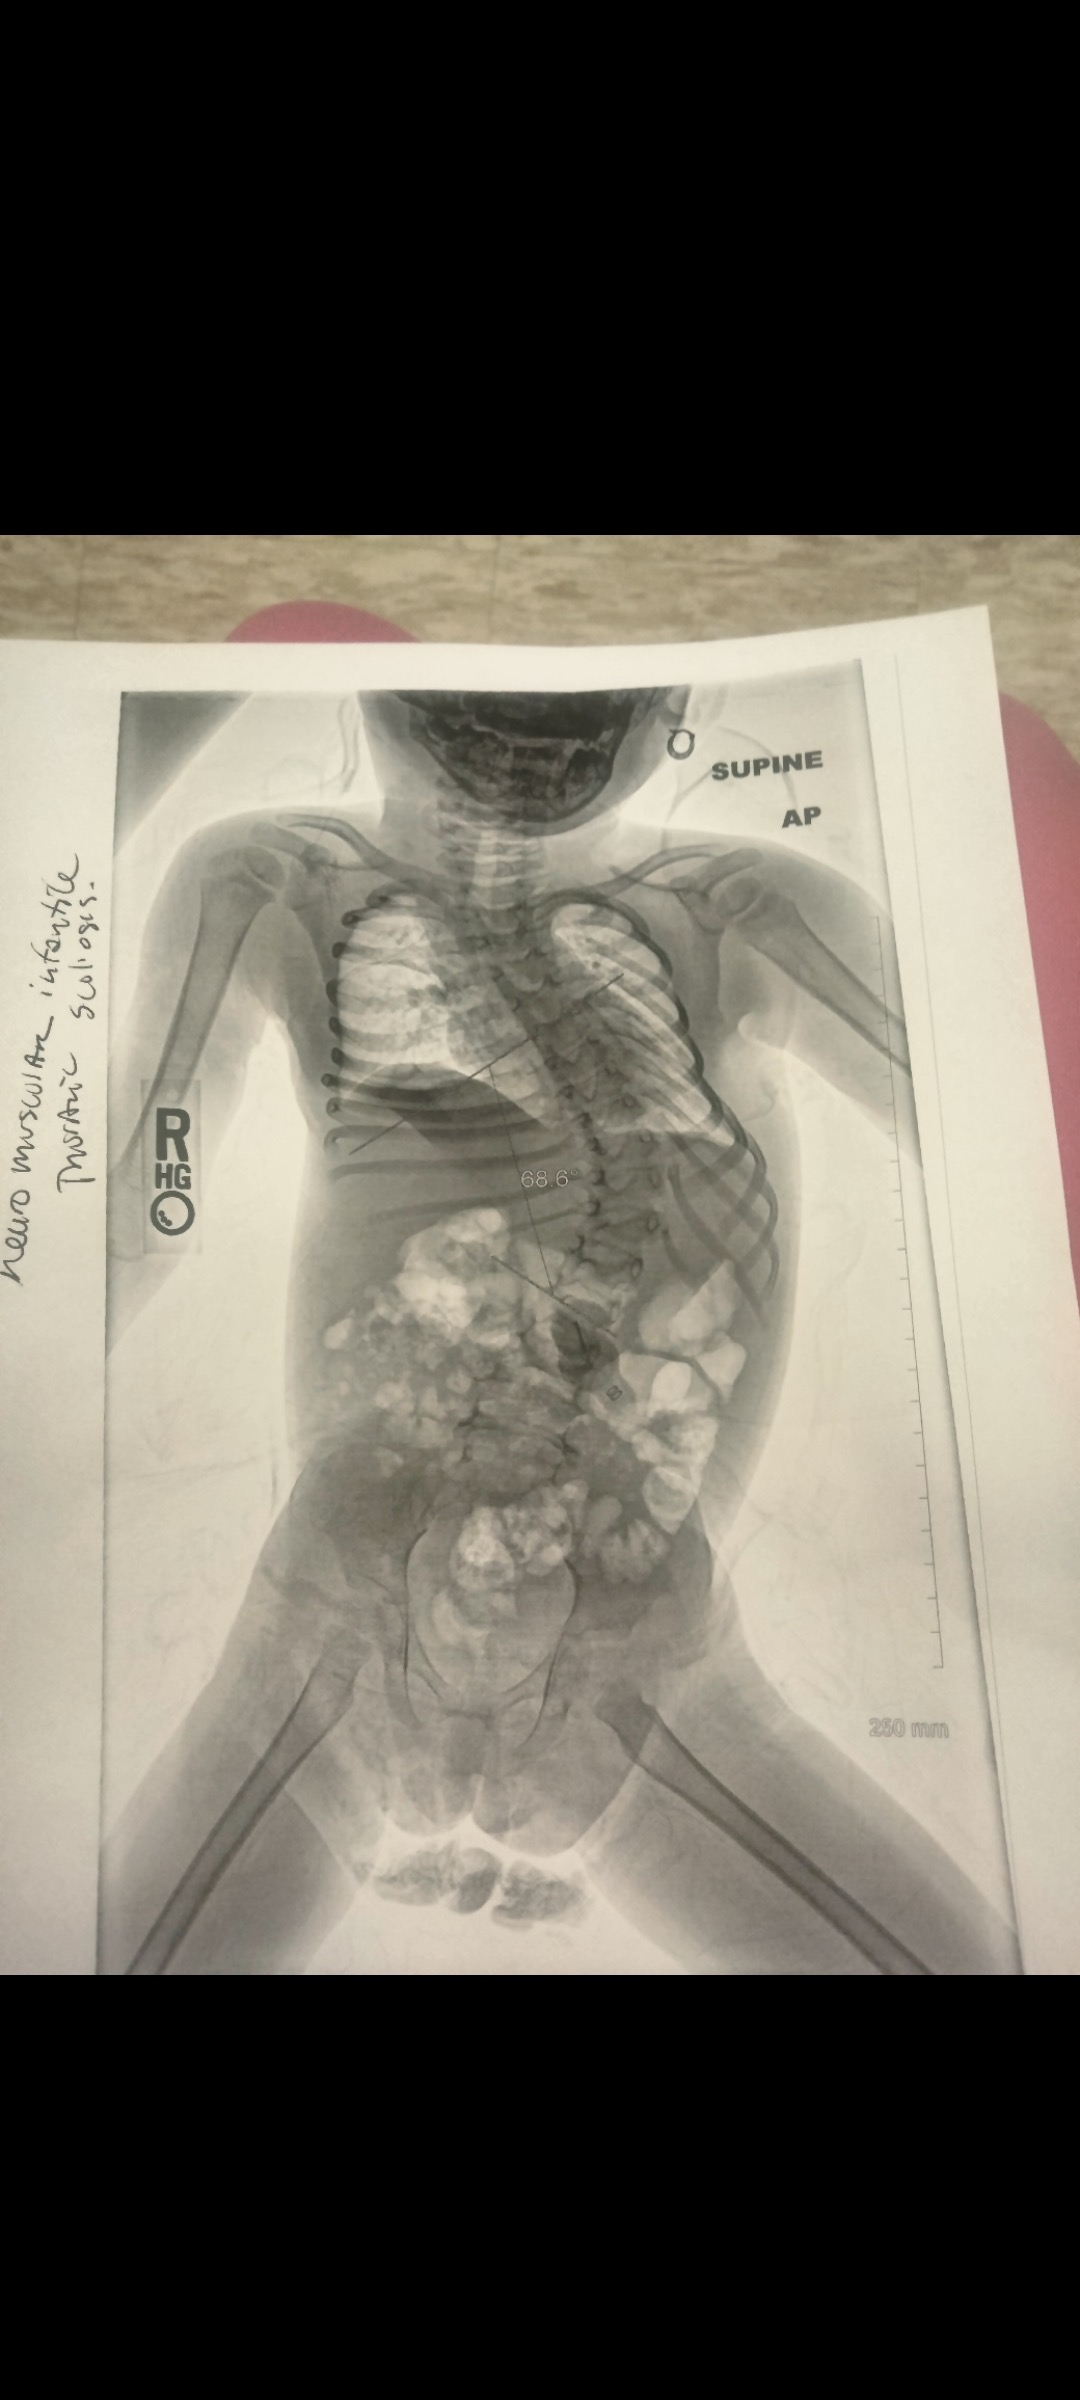

Ma’Nyla is our bright, loving little girl who has always brought joy and laughter to everyone around her. Her life changed in an instant due to a spinal cord injury caused by medical negligence. While we continue to seek answers and justice, our focus is now on her survival and recovery. The ICU has become her home for weeks, and she remains on a ventilator because her lungs are too weak to handle even the smallest infections. Simple illnesses, like a cold, have become life-threatening due to the severe curve in her spine, making every breath a battle. What started as a simple cold quickly became life-threatening because of the spinal cord injury she sustained from medical negligence. The injury caused a severe curve in her spine, which now weakens her lungs and makes even minor illnesses dangerous. Every day, Ma’Nyla battles to breathe while we hold onto faith and surround her with love. As we stay by her side, unable to work and focused entirely on her care, we’re asking for prayers, love, and any support to help us stay strong through this unimaginable journey.